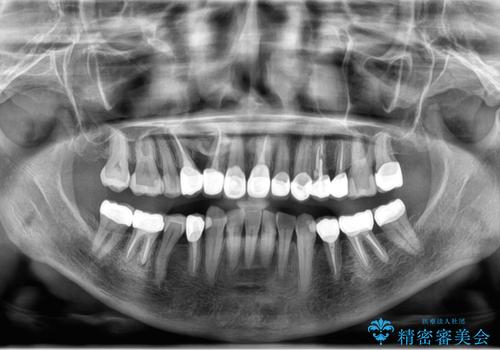

50代女性 銀歯をとって白いつめものに 全体的な治療

- 銀歯や被せ物のやり替えをご希望で来院。悪いところはすべて治していきたいとのことでした。

根の治療を含めてしっかりやり直しを行いました。

本数も多く、時間はかかりましたが、しっかり通いきっていただきました。